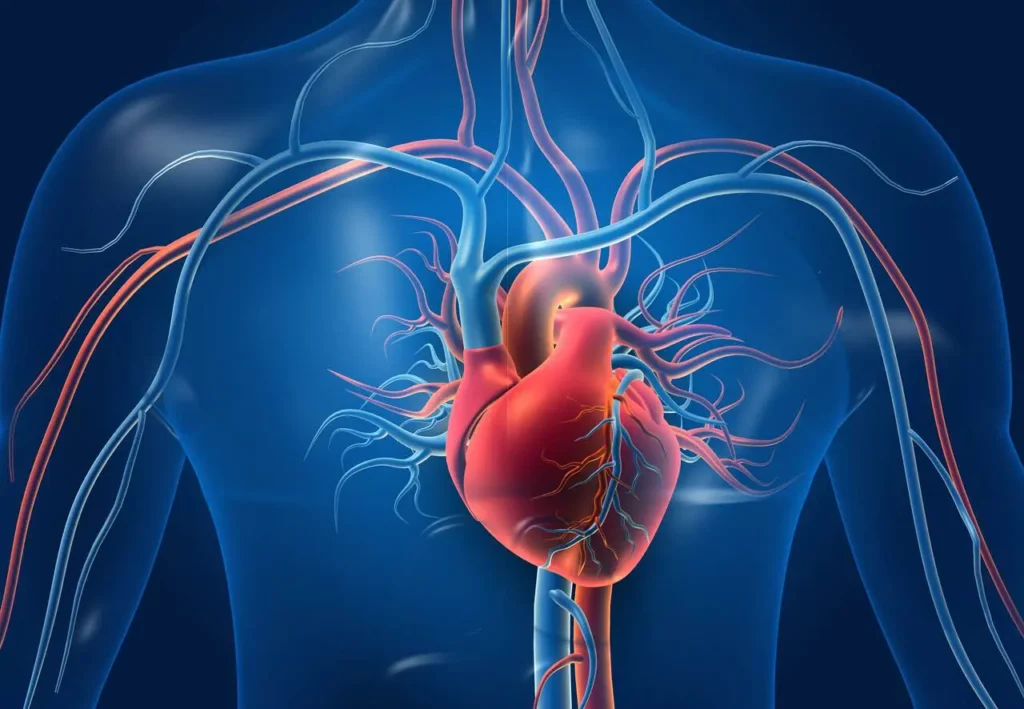

Come capire se il cuore non pompa bene? Quando il cuore non pompa bene, il corpo invia segnali specifici che possono essere osservati attraverso sintomi fisici e alterazioni nei parametri vitali. Questa condizione è spesso legata a problemi di insufficienza cardiaca, in cui il cuore non riesce a pompare sangue a sufficienza per soddisfare le necessità del corpo. Ecco come capire se il cuore potrebbe avere difficoltà nel funzionamento.

1. Segnali e sintomi di insufficienza cardiaca

Un cuore che non pompa bene invia segnali specifici. Riconoscere questi sintomi e intervenire tempestivamente può fare la differenza per la tua salute cardiaca.